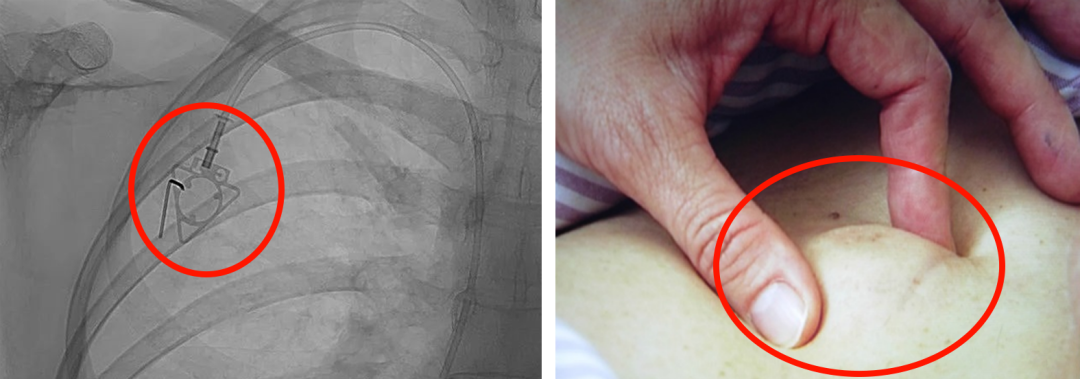

輸液港,臨床上也稱為PORT,是為了減輕藥物對(duì)患者血管刺激而置入體內(nèi)的專業(yè)輸液裝置。它分為三部分:無損傷針、置入靜脈的導(dǎo)管、埋藏在皮下與輸液針連接的注射座(港體)。注射座連接插入大靜脈的導(dǎo)管形成長(zhǎng)期血管通路,發(fā)揮類似港口的作用,故稱作“輸液港”。

(1)輸液港輸注藥物直達(dá)大血管,手臂不會(huì)產(chǎn)生明顯的不適。由于每次穿刺的是皮下置入的港,可以減少針頭對(duì)血管的刺入次數(shù),操作簡(jiǎn)單,對(duì)患者的血管起到保護(hù)作用;

(2)輸液港放置在皮下,不易被別人發(fā)現(xiàn),具有隱秘性;洗澡,日常生活不受限制;

(3)由于輸液港完全埋藏在體內(nèi),不易受到感染;